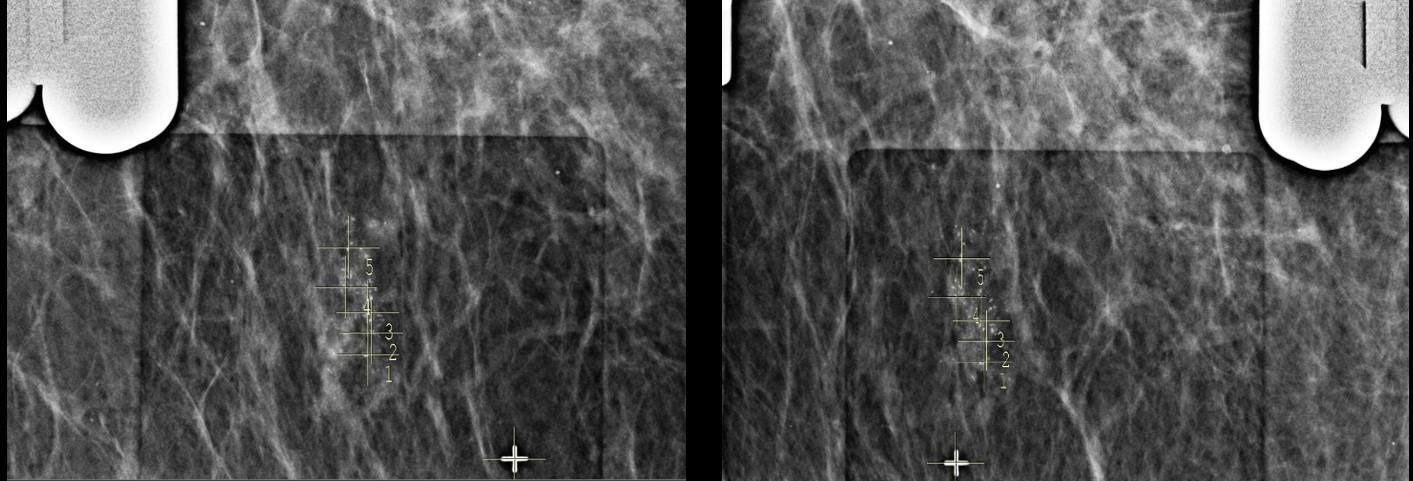

Realizado a análise do menor trajeto para acessar a área referida, a paciente foi posicionada em oblíqua, através da entrada de raios X em médio-lateral com angulação de 50°. As marcações dos alvos foram feitas em duas abordagens distintas (imagens 3 e 6), com objetivo de atingir a maior quantidade de microcalcificações. O procedimento foi realizado sem intercorrências e os fragmentos obtidos foram submetidos a um estudo radiológico demonstrando espécimens adequados com a presença de microcalcificações na amostra (imagens 5 e 7). O resultado anátomo-patológico obtido foi de carcinoma ductal in situ.